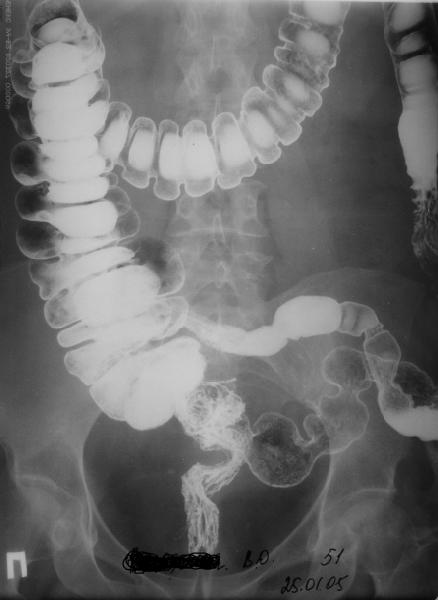

Грыжа сквозь крыло таза

Женщина 51 г. полтора года назад попала в автоаварию, был перелом таза и голени, лечилась консервативно, на вытяжении недель 6, потомх одила с костылями.

Через 3 мес. после травмы обратила внимание на выпячивание сбоку таза. Картина на сегодня на рентгенограммах и фото. Похоже, это грыжа сквозь несросшееся крыло подвздошной кости. Как тут правильно сформулировать диагноз? Что лучше предпринять для ликвидации грыжи?